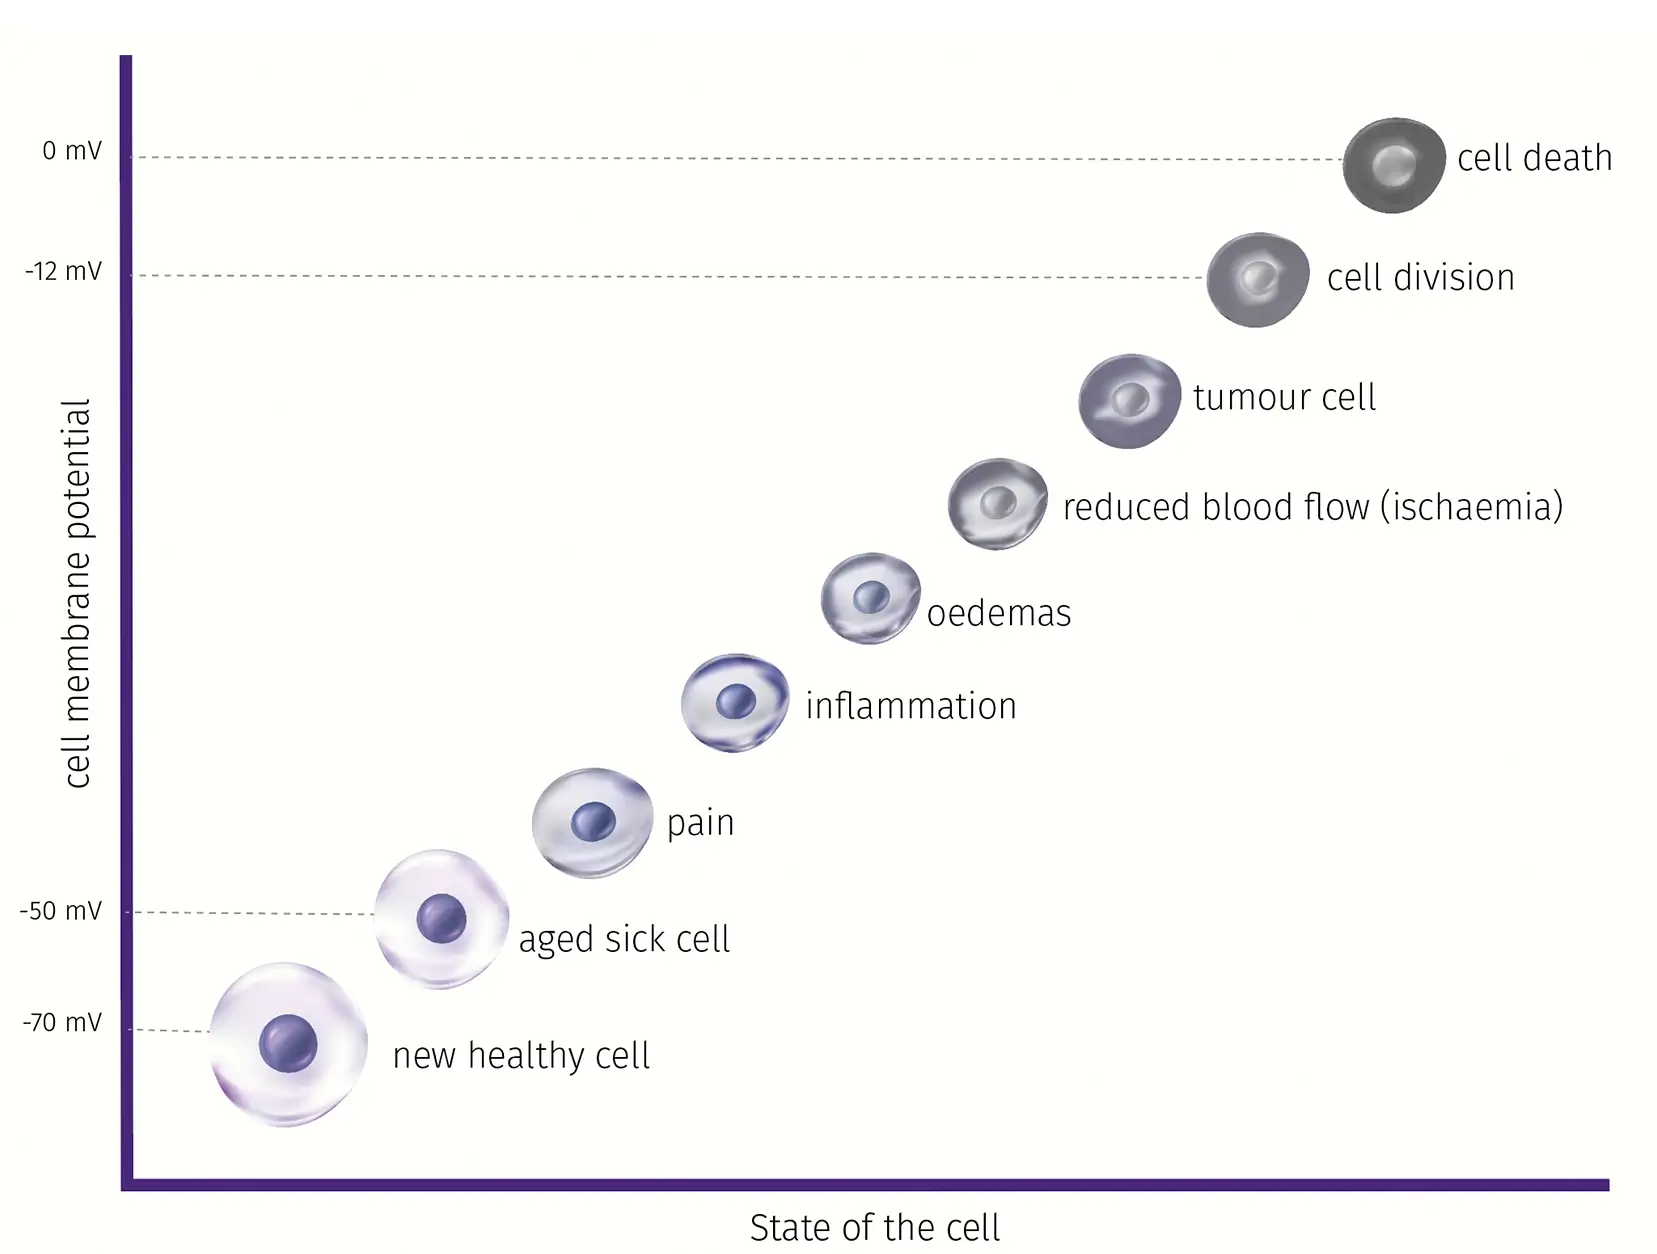

Terve solu tarvitsee riittävän solukalvojännitteen (noin -70 mV – -90 mV) ylläpitääkseen säätelyprosessejaan. Kaikilla sairauksilla ja vammoilla on yksi yhteinen piirre: sairastuneilla soluilla ei enää ole lainkaan tai vain osittain oma luonnollinen solukalvopotentiaali.

Terve solu tarvitsee riittävän solukalvopotentiaalin (noin -70mV – -90mV) ylläpitääkseen säätelyprosessejaan. Jos jännite laskee, se voi aiheuttaa kipua, tulehdusta, turvotusta tai sepelvaltimotaudin sekä muita patologioita. Ioni-induktiokenttä stimuloi heikentyneet kehon solut ja nostaa ne terveeseen jännitepotentiaaliinsa.